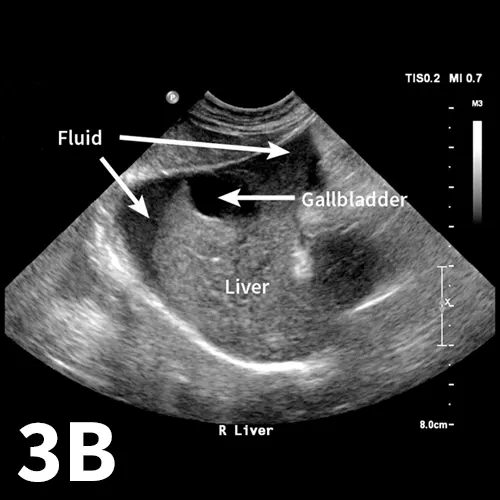

The aFAST examination divides the abdomen into 4 quadrants. A good way to perform the examination is to use a clock-face analogy and begin at the 12-o’clock position (Clock-face). The starting position, designated the diaphragmatic–hepatic (DH) position, is caudal to the xiphoid process; it is useful for finding fluid between liver lobes and the diaphragm. The next quadrant lies at the 3-o’clock position over the left flank and is designated the spleno–renal (SR) position. Both the spleen and left kidney should be visible within this region. At the 6-o’clock position over the caudal abdomen, the urinary bladder and colon can be seen, making this window the cysto–colic (CC) position. The final quadrant within the aFAST examination is over the right flank at the 9-o’clock position, designated the hepato–renal (HR) position. The right kidney and liver should be visible within this region.1,4

As with many skills in veterinary medicine, becoming proficient at the aFAST examination and maneuvering the ultrasound probe requires practice. The aFAST examination can be easy to learn and a good way to identify peritoneal fluid in patients with recent motor vehicle trauma. The aFAST examination also has applications in patients that present with an acute abdomen but no known trauma. With gained proficiency, clinicians may be able to diagnose other conditions (eg, splenic mass, gallbladder mucocele) that could require acute intervention.